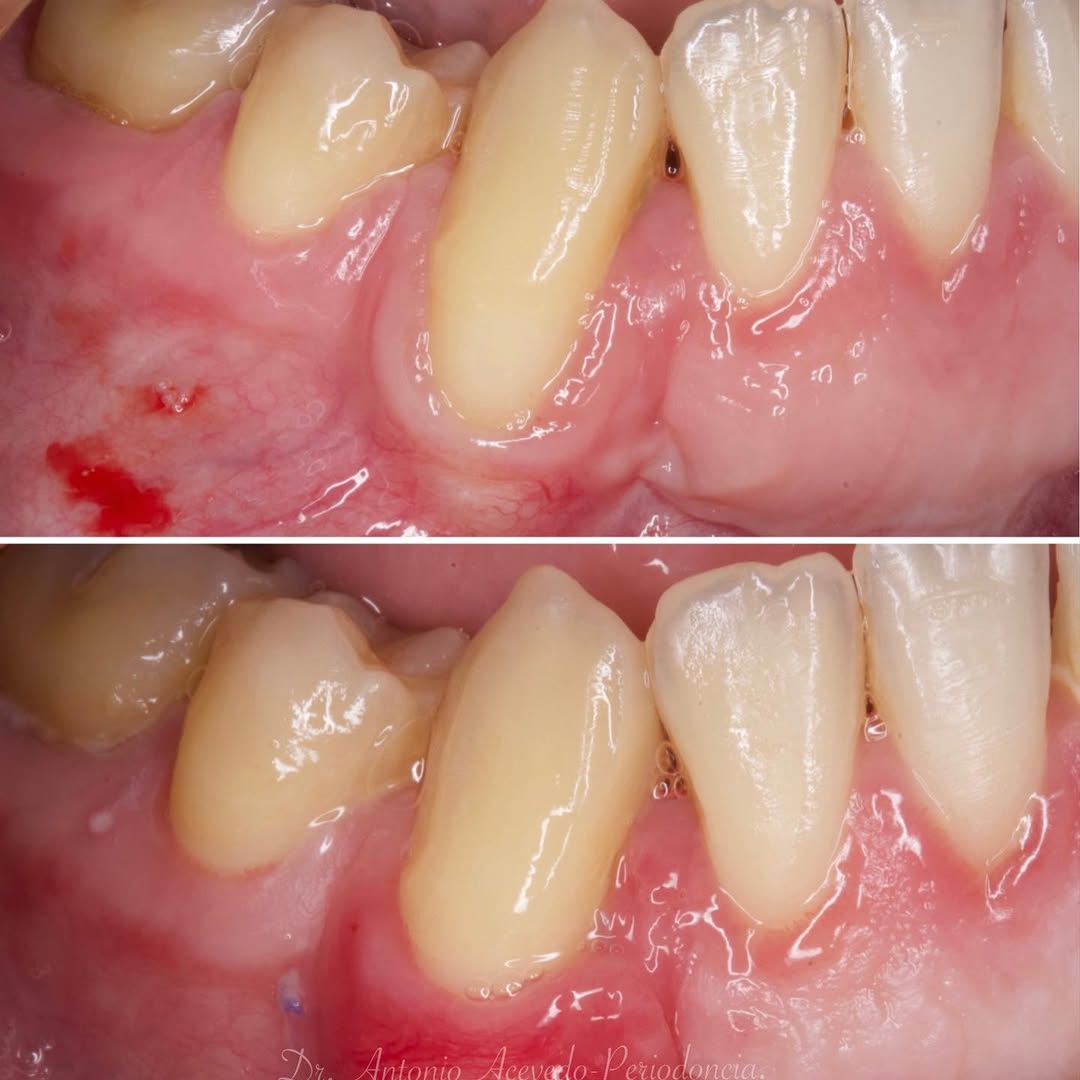

Durante una mañana, asistirás a una Cirugía Mucogingival de recubrimiento radicular de recesiones múltiples en IV y V sextante (36 a 43).

Gracias al uso del microscopio y a la proyección en tiempo real en pantalla, verás exactamente lo mismo que veo yo durante la cirugía, sin tener que estar

Podrás asistir a la planificación de casos y cirugía de injerto de tejido conectivo. Factores determinantes y elección de la técnica adecuada. Sumérgete en un protocolo predecible y técnicamente correcto para obtener resultados óptimos.